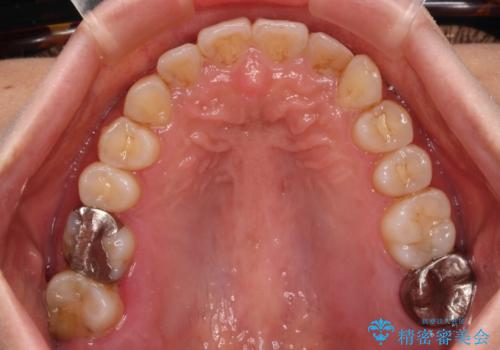

前歯のデコボコとクロスバイト インビザラインによる矯正治療

懸念されたとおり、右下のクラウン部分が全く咬み合わず、仕上げの段階で治療期間が長くなりました。